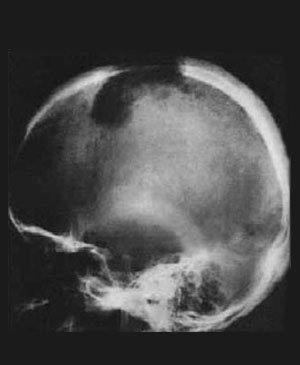

악성종양의 두개골 전이(Cranial metastasis)

병소(focus)는 거의 예외없이 용골성(osteolytic) 이다

용골성병소(osteolytic focus)의 변연은 보통 불명 료 또는 불규칙하거나 또는 침윤성 파괴를 나타 낸다

보통 병소 주변의 골경화 또는 골신생을 수반하지 않는다